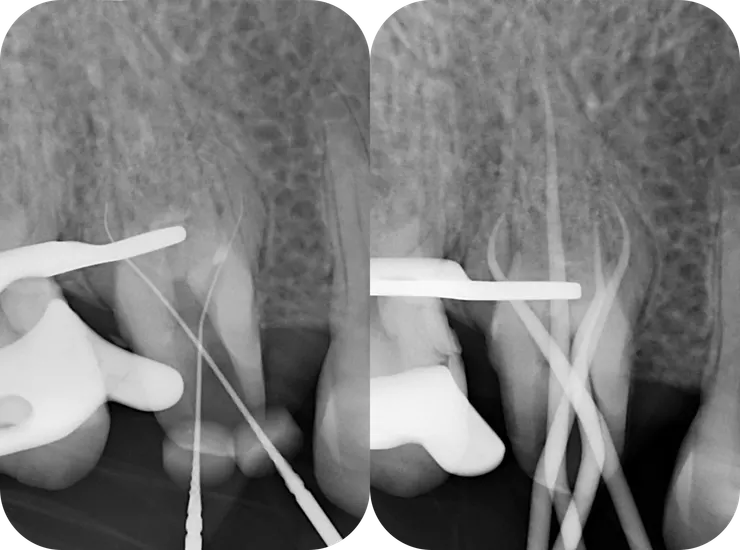

左圖:

確認 file 找到正確的路已順利過彎。

可以看到 file 中上段是 "自由"的。

右圖:

用 hand file 建立 glide path 後,後面的事就是小事了......

從 initial v.s. RCF 可以看得出來,因為 DB & MB2 canal 過彎不易,犧牲了不少 pericervical dentin. DB orifice 上方也是類似的情況,有一區蓋過來的 dentin. 但因為 DB 洞明顯的比 MB2 洞大多了,所以我沒多加處理。就這樣試著把 file 督進去......

但還好因為 heat treated NiTi file (PTG F1) 過彎能力佳,以及過程中且戰且走地以正確的順序使用正確的工具,而因此不需要把第一個彎以上全部拉直,得以保留足夠的 pericervical dentin.